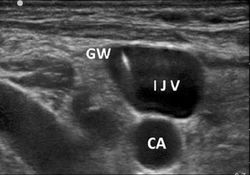

US guided IJV insertion (can be applied to femoral vein): Strict use of sterile technique throughout procedure is essential to preventing line infection. Provider should be sterilely gowned and gloved and patient should be sterilely draped. If patient can tolerate it, placement of patient in slight Trendelenburg position allows increased blood flow to the IJV. Prior to procedure flush the catheter with normal saline, cap the ends of the catheter and pull back (‘load’) the guidewire into its sheath. Cleanse skin with chlorhexidine and drape patient. Place vascular US probe into sterile sheath. On US identify the vein and distinguish it from the carotid artery:

1. vein will be fully compressible compared to carotid artery

2. vein will not have pulsatile flow on auditory Doppler

3. vein will not have pulsatile color flow. Once the vein is identified inject a small amount of lidocaine subcutaneously above anticipated insertion site.

IJV ultrasound.png